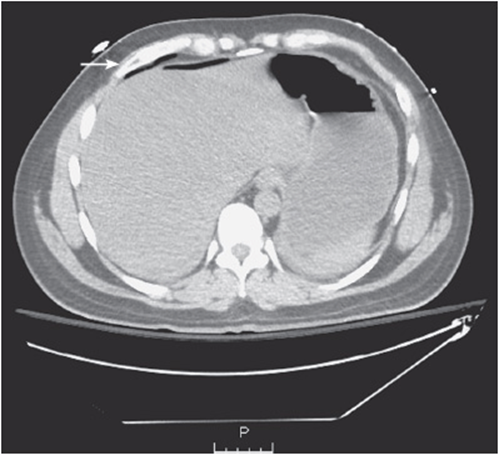

• An easy trick is to look for free air using the “lung window” (see Figure 56-2).

Figure 56-2. Quickly looking at the abdominal CT using the lung window helps better visualization of any abnormal free air versus intraluminal air in the peritoneal cavity.

• Free air can be normal in the immediate postoperative phase (up to 1 week), but is otherwise often an indication for emergent surgical intervention.